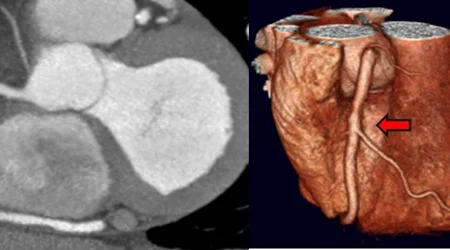

ابزار اصلی آنژیوگرافی قلب ، دستگاه آنژیوگرافی است که منبع تولید "اشعه ایکس" (X-Ray) است. از اشعه ایکس برای انجام بسیاری از تصاویر رادیولوژی و سی تی اسکن استفاده می شود. این اشعه در برخورد با بافت نرم بدن به راحتی عبور می کند ولی در مقابل بافت های سفت بدن ، بسته به نوع بافت ، به درجات مختلفی جذب بافت شده و در تصاویر ایجاد شده مناطق سیاه رنگ ایجاد می کند. قلب و عروق جزو بافت های نرم محسوب می شوند که اشعه ایکس به راحتی از آنها عبور کرده و تصویر مشخصی از جریان خون یا شکل قلب و عروق ، نمی تواند ایجاد کند. به همین منظور از مواد تزریقی که بتوانند اشعه ایکس را جذب کنند ، استفاده می شود. آنژیوگرافی در اصل تزریق ماده حاجب داخل رگها و حفرات قلب و تصویریرداری همزمان با اشعه ایکس است تا تصویری از همان رگ یا حفره در تصاویر آنژیوگرافی ایجاد شود. به این ترتیب اگر تنگی یا انسدادی در مسیر رگ یا حفرات قلب باشد ، ماده حاجب به آن نواحی نخواهد رسید و لذا تصویری از این مناطق هم ایجاد نخواهد شد.